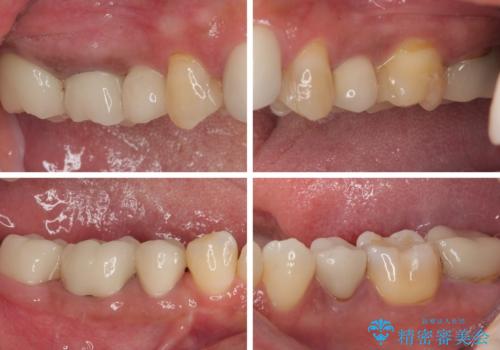

右下のむし歯が歯肉縁下に及んでおり、歯周外科処置(歯冠長延長術)を行った上で、根管治療を行い、状態を整えて補綴治療を行うこととしました。

上顎前歯の根尖病変に痛みがありましたが、既に前歯が補綴治療済みであっため、外科的歯内療法(歯根端切除術)を行うことで解決することとしました。

新幹線で通院をされていたため、極力診療回数を減らして、一度にまとめて多くの処置を行うことで負担を軽減しました。